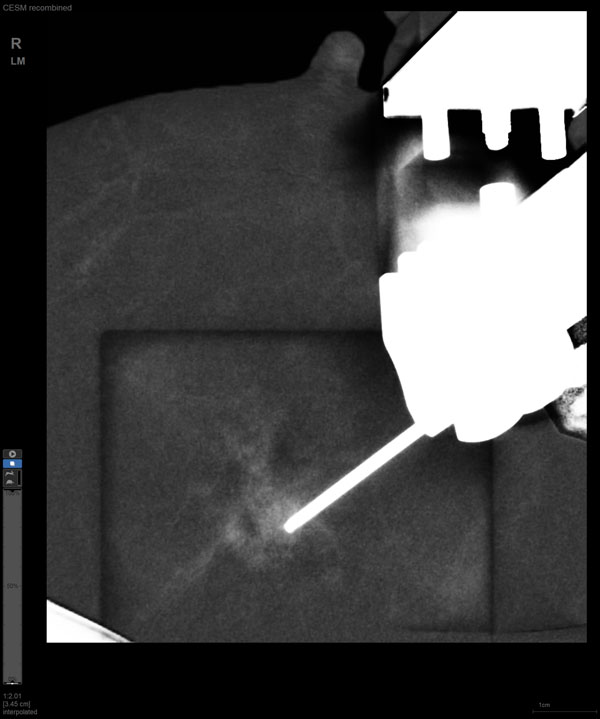

某患者增强磁共振成像MRI显示肿瘤周边有活性,中心区域有组织坏死。为得到准确的病理结果,穿刺靶区需避开肿物坏死区域。在与患者主管医生充分讨论后,放射科医生为患者行CEM引导下穿刺活检术。术中,CEM检查肿物同样显示为环形强化,巧妙避开坏死区域后,穿刺靶区选择了肿物增强早期明显强化区域,术程顺利,仅用时15分钟。术后该患者病理结果为浸润性导管癌Ⅱ级。

国内首台具有数字乳腺断层摄影(DBT)和CEM引导下穿刺功能的X线机

随着计算机技术发展和乳腺X线机硬件的提升,CEM与立体定向活检技术相结合的CEM引导下穿刺活检术开始在临床应用。与MRI引导的乳腺穿刺活检相比,CEM穿刺活检无需抗核磁耗材,成本更低,检查速度更快。据国外研究文献报道,CEM引导的穿刺活检有可能成为MRI引导的乳腺穿刺活检的有效替代方案。